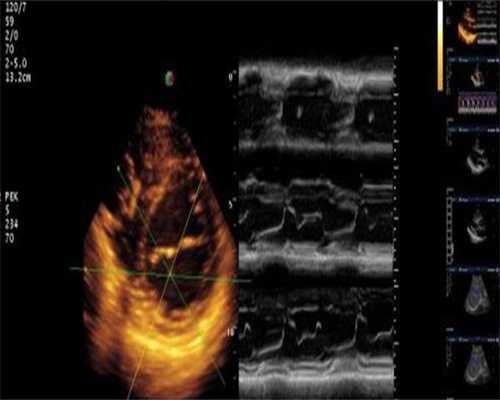

首先,消毒,然后躺在手术台上,试管婴儿医生将带有穿刺架的阴道探针插入阴道,正如通常的B超检查一样,医生将清楚地看到卵泡的位置,然后使用针从阴道进入卵巢,将吸出大小合适的卵泡。